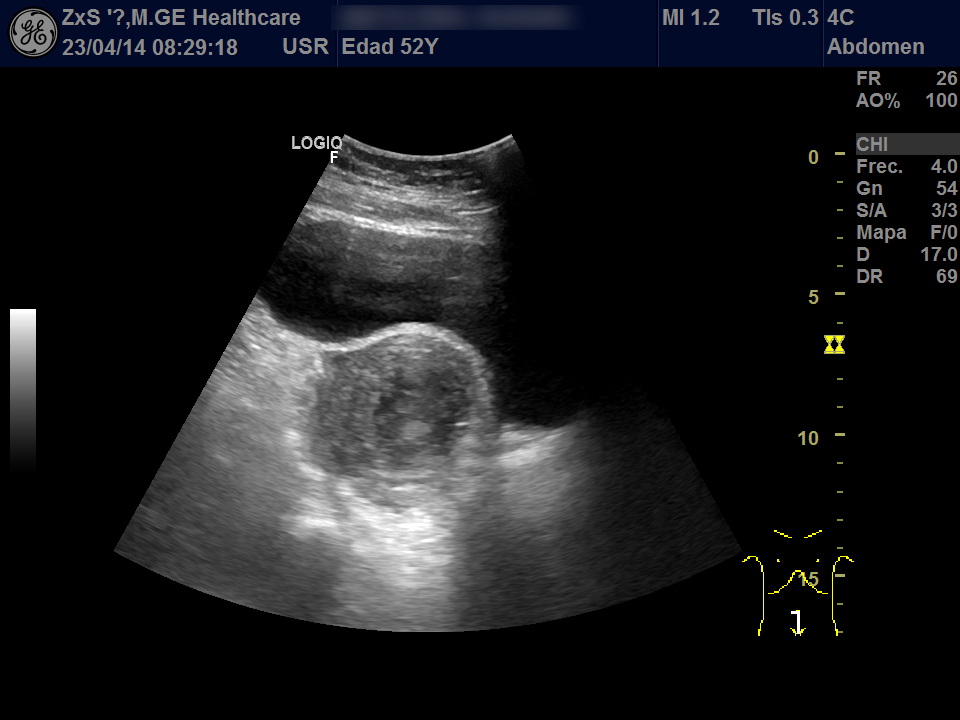

Hígado de bordes lisos y ángulo agudo, aspecto heterogéneo, no se observan LOES. Vía biliar extra e intrahepática no dilatada. Vesícula poco replecionada sin imágenes en su interior, Murphy ecográfico negativo. Ambos riñones de localización y tamaño normal. Buena diferenciación córtico-sinusal y en riñón derecho discreto aumento del tamaño de la pelvis renal compatible con hidronefrosis grado 2. Vejiga bien replecionada sin ecos en su interior. Se objetiva útero de tamaño normal con una imagen hiperecogénica que corresponde a DIU y en la zona derecha una lesión redondeada de aproximadamente 5,5 x 6,5 de diámetro de contenido heterogéneo que dudamos si puede corresponder a masa ovárica desconocida. Se deriva al hospital por sospecha de masa ovárica.